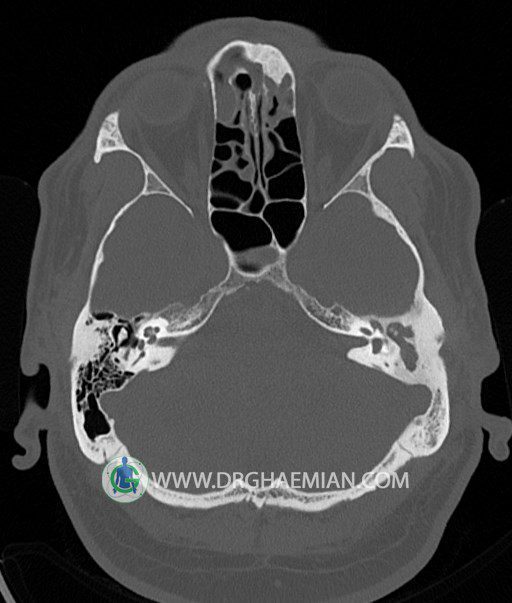

سی تی اسکن گوش داخلی به رادیولوژیست اجازه می دهد تا سطوح مختلف، یا اسلایس هایی از استخوان های که از جمجه به گوش می روند را از طریق امواج ایکس چرخشی مشاهده کند. در این کیس اودیت مدیا، ماستوئیدیت مزمن، اوتیت خارجی، انحراف سپتوم بینی، کونکا بولوزا و افزایش ضخامت سینوس ها مشاهده می شود.

در HRCT از استخوان تمپورال با مقاطع آگزيال ، ساژيتال و کرونال ظريف ( 0.6 mm ) :

– نماي کوکلهآي دو طرف با 2.5 دور گردش مجرا

– نماي cochlear aqueduct

– نماي semicircular canal خلفي ، لترال ، فوقاني و وستيبول

– استخوانچه هاي گوش داخلي شامل malleus ، incus و stapes (دنسيتي و رديف استخوانچه ها )

– نماي oval window و round window ، tympanic cavity ، attic و کانال گوش داخلي

– انحراف سپتوم مياني بيني به راست

– کونکا بولوزا در کونکاي مياني چپ و

– افزايش ضخامت مخاطي در سينوس هاي اتموئيد و ماگزيلاري